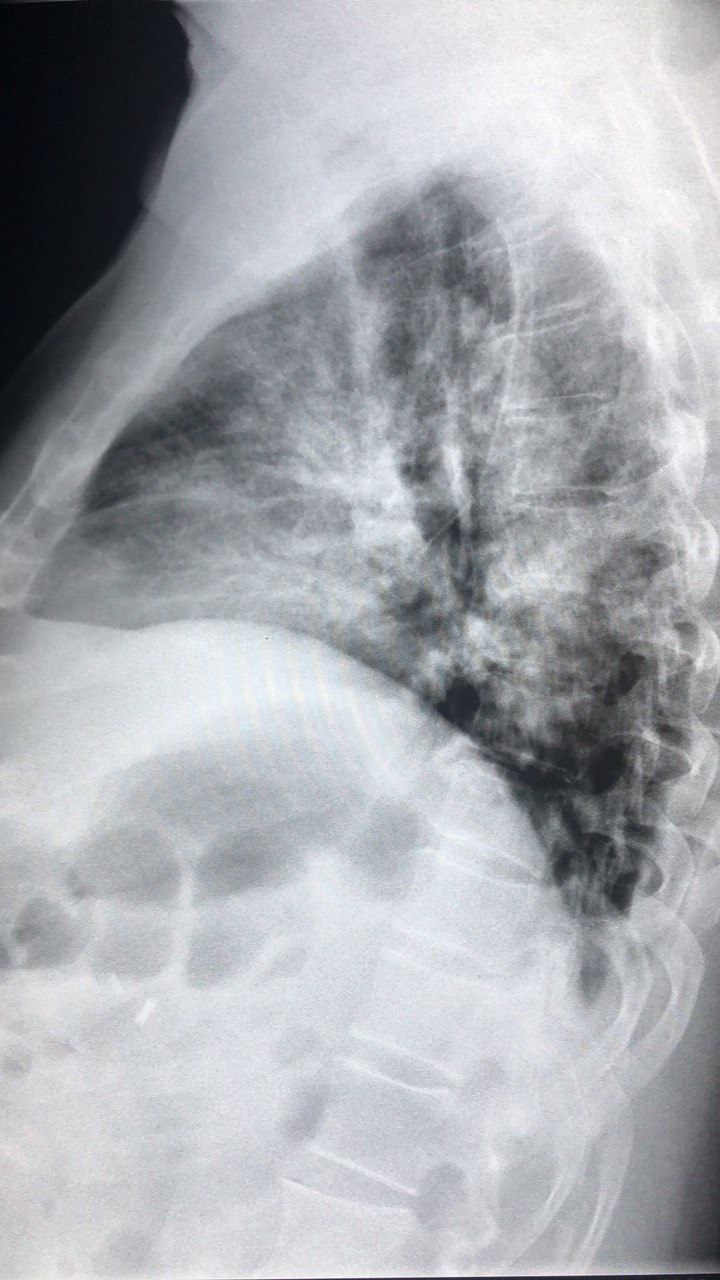

Добрый вечер, коллеги. М, 60 лет. А анамнезе рак правого лёгкого с мтс. Сейчас темп 37.2, кашель с мокротой. Пришли исключить пневмонию.

По-моему нету пневмонии, вы как считаете?

Справа в нижней доле - участок инфильтрации, гидроторакс

S6,S4-5,возмоно выпот ,МСКТ

И все таки пришёл ковид сегодня

Правосторонная плевро пневмония